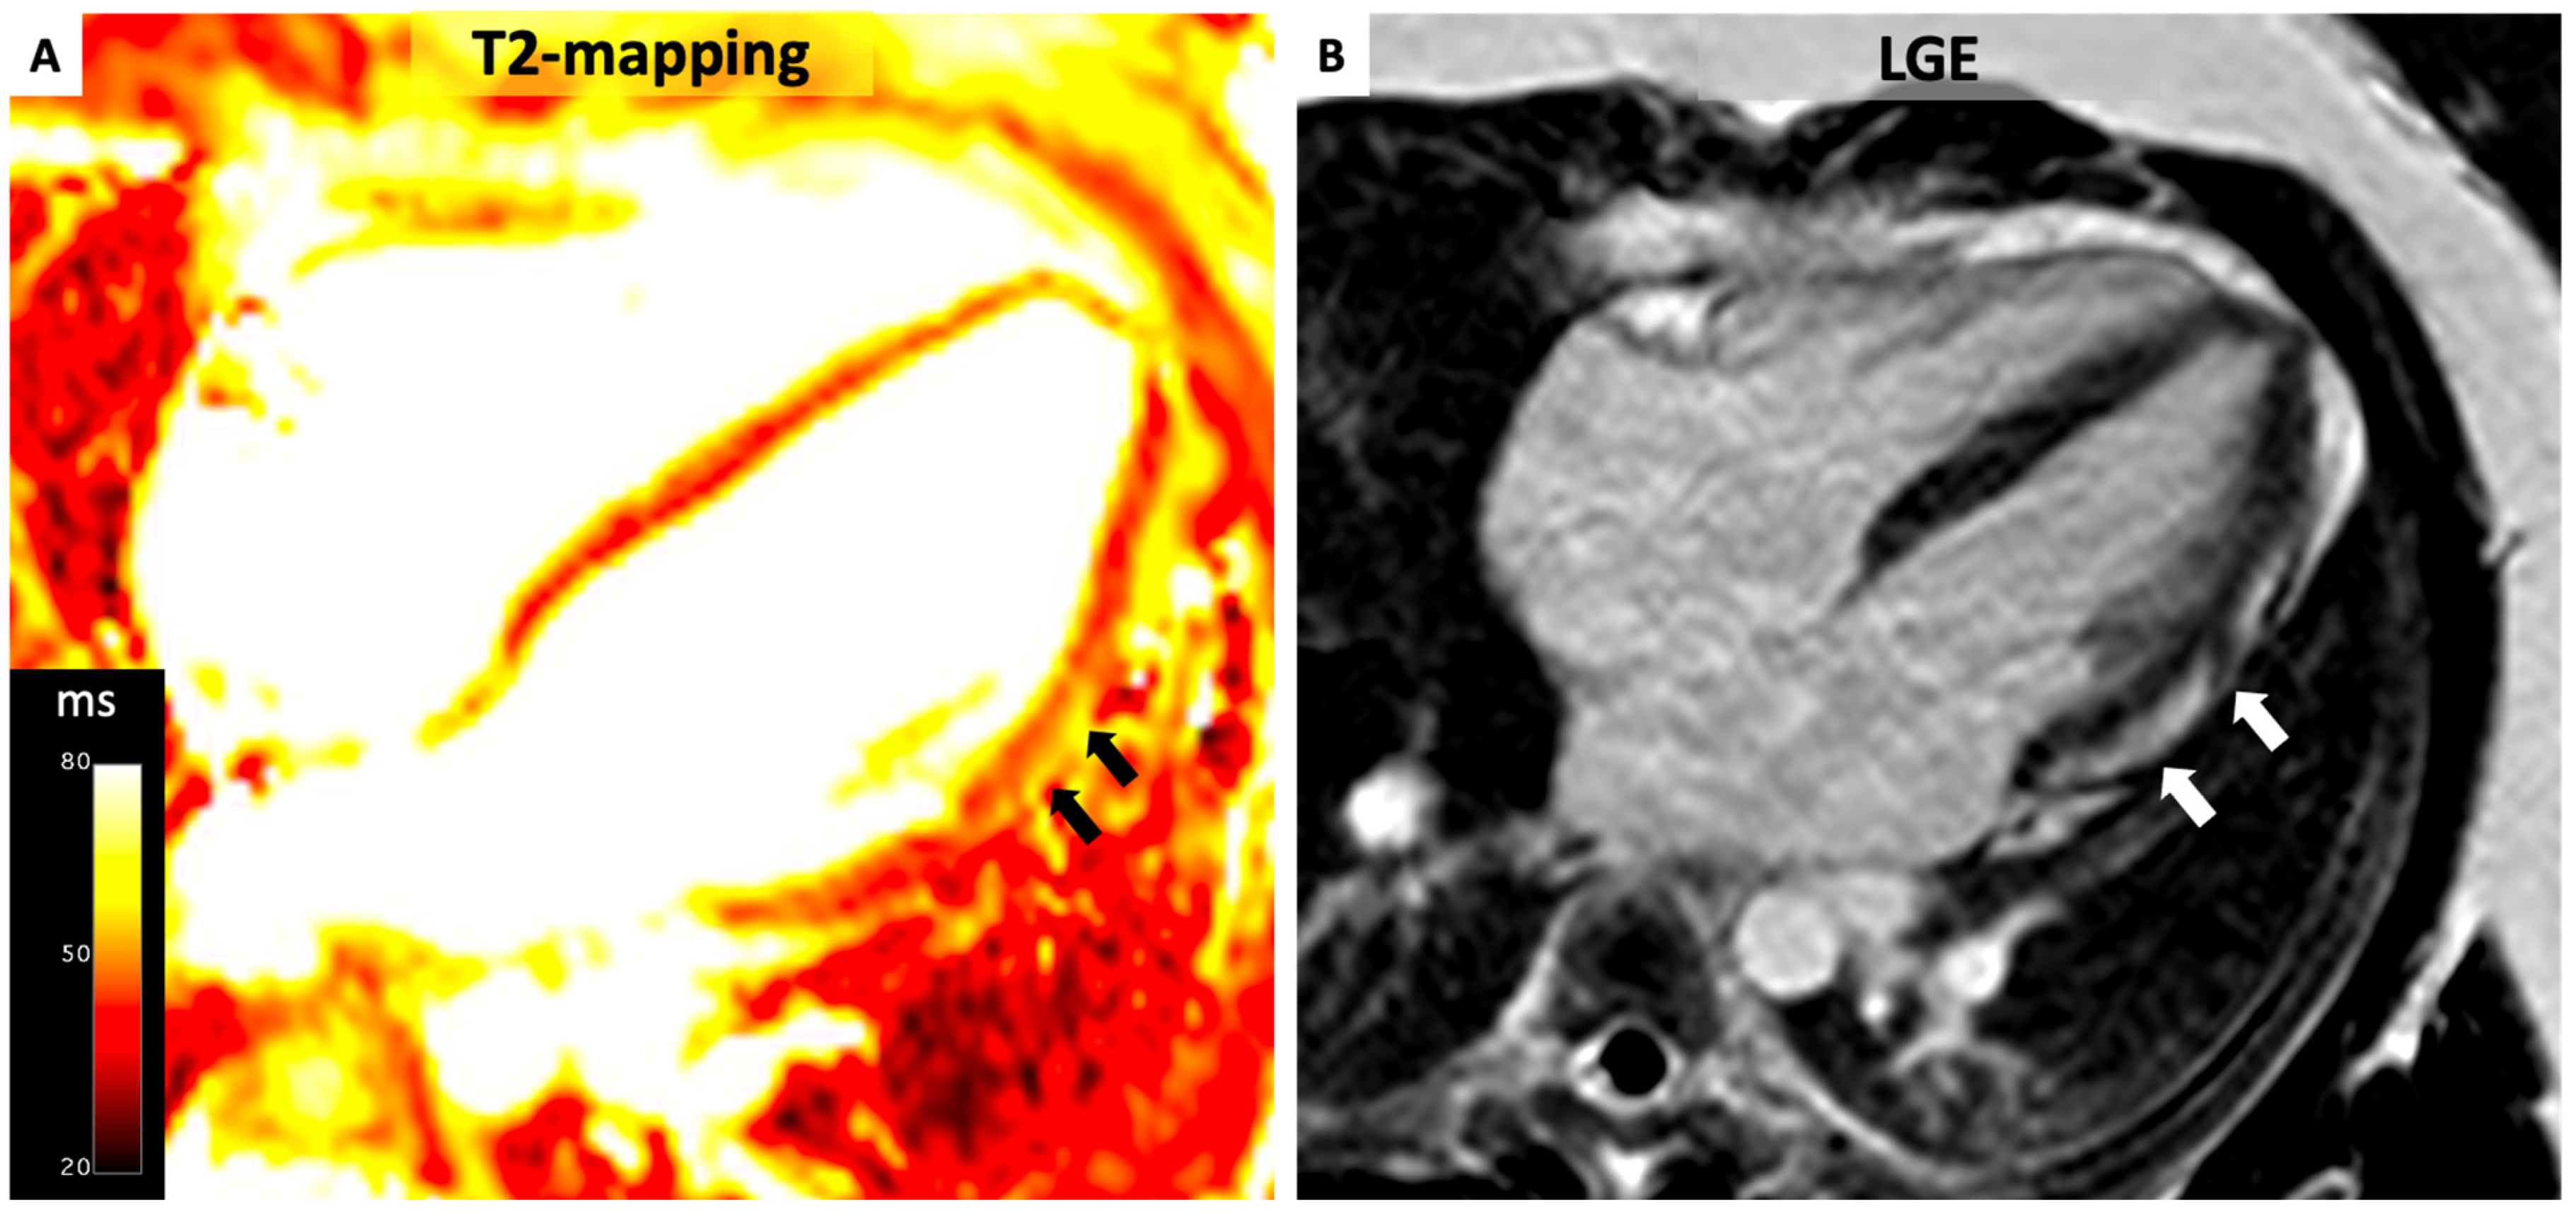

4.3. Myocarditis

4.4. Cardiac Sarcoidosis